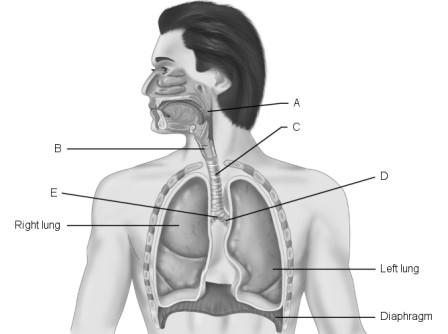

Main (primary) bronchus.

D

Larynx.

B